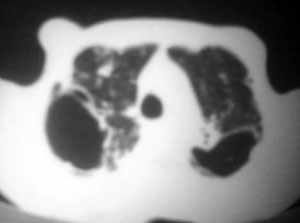

以下是引用逸风在2006-9-12 14:57:00的发言:[br]ct显示双肺上叶点片状及纤维索条状密度不均影,肺野外带近胸膜可见大小不等的含气空腔,壁略厚,境界清晰,未见液平面,中下肺野散在小片状及点状高密度影;纵隔内显示点状钙化,未见明显淋巴结肿大,构成胸廓诸骨未见明显异常.[br]诊断意见:1.双肺结核合并支气管播散;2.双肺上肺大泡.